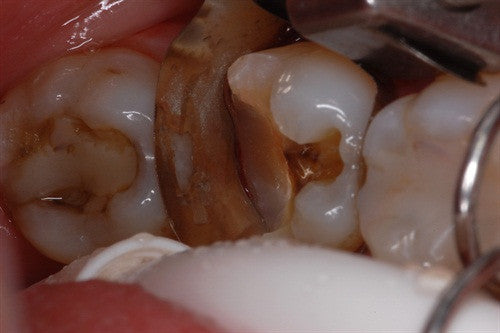

Recurrent caries under crown - "Thinking outside of the box" by Dr. Ahmad Fayad

Posted on March 22 2023

Introduction: This case was completed by Dr. Ahmad Fayad of Lessard Dental located in Alberta, Canada. Food impaction area that caused massive carious lesion at the distal of the lower... Read More